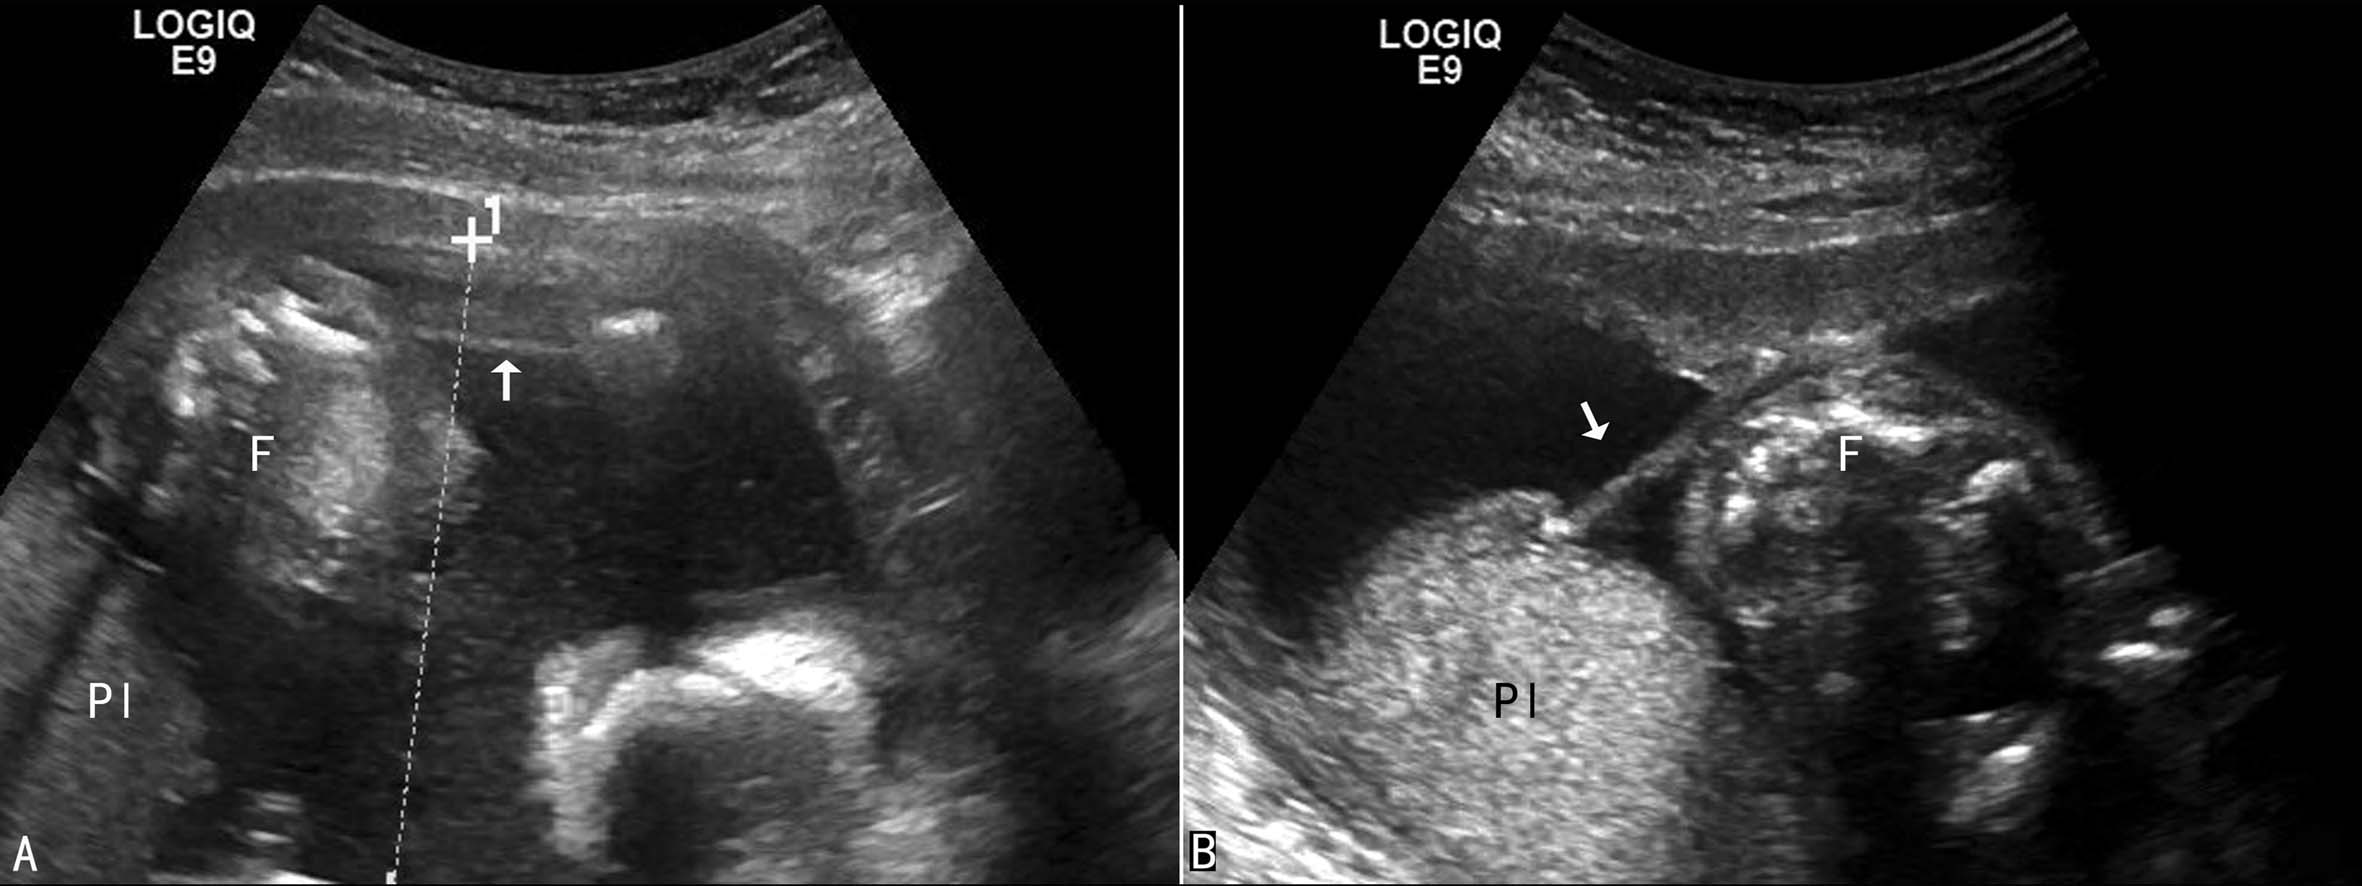

羊膜腔内可见不规则单条或多条索带状回声连于羊膜腔的不同部位,或连于羊膜腔的一侧壁和胎体的某一部位,胎体位置固定,活动受限(图4)。追踪扫查可以不同的畸形。几乎所有的病例均显示为多发的、非系统性的畸形。主要畸形可分为三类:肢体异常,颅面畸形,躯干异常。肢体异常可显示为多种不对称性畸形,如多指(趾)、并指(趾)、指(趾)缺失、肢体纵裂、收缩环,离断等(图5);颅面畸形包括颅骨缺损、脑组织膨出和缺损、颅裂、无脑、颅骨无钙化或钙化不全,并常可发生面裂、额裂、唇腭裂、颌裂、耳裂等。常见的躯干畸形包括内脏异常、脐膨出、腹裂、缩复环等。

图4羊膜索带声像图